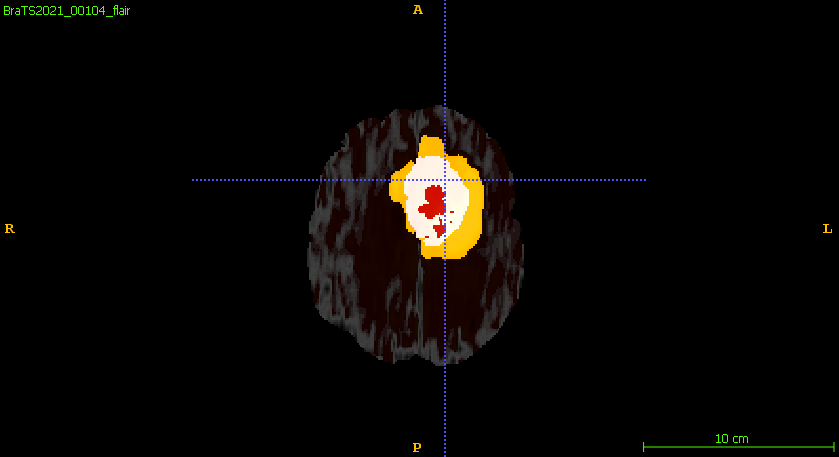

Furthermore, Figure 6 compares the ground truth on different planar views and the predicted segmentation labels corresponding to those views in the training set. The segmentation network demonstrates robust performance, accurately capturing the intricate details of tumor boundaries and structures across all planar views. The achieved DSC for the samples shown is 0.943 for ET, 0.957 for WT, and 0.949 for TC, reflecting the network’s high precision and reliability in segmenting different tumor regions. These results highlight the model’s effectiveness in generating segmentation outputs closely aligned with the ground truth.

Figure 6: Qualitative comparisons include (a–c) input FLAIR images with ground truth overlaid across axial, sagittal, and coronal views, (d–f) ground truth across the planar views, and (g–i) the corresponding predicted segmentation labels from the training set for each view.